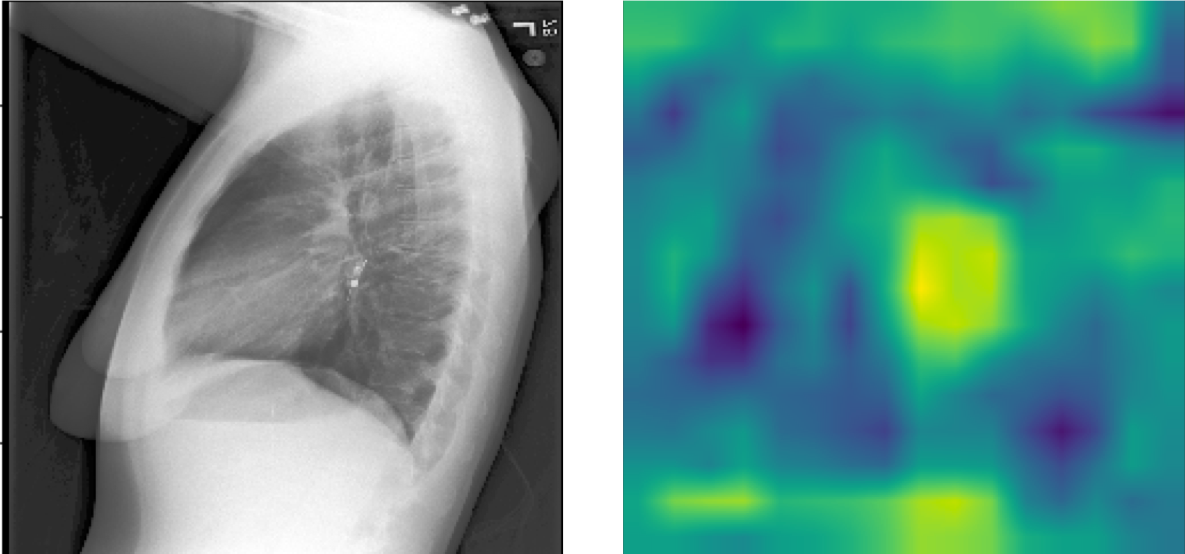

The pre-trained TIMNet used in this study has a text-image matching performance of 74% accuracy and 0.83 auROC. Table I shows the relevant results of the evaluation. Figure 7 shows CAM visualizations of TIMNet on the text-image matching task. The findings of the radiology reports are displayed below the images. The CAMs suggest that the decisions made by TIMNet are reasonable. For instance, in Figure 7(a), the radiology report mentions radiopaque densities in the mid to distal esophagus, and the CAM appears to show that in the middle part of the image. For Figure 7(b), the radiology report indicates increased right-sided pleural effusion, and CAM shows more significant contributions near the effusion areas on the right-hand side of the figure. Figure 7(c) shows a similar correspondence between the CAM-based image segment contributions to the model decision and the textual report.

Refer to caption

(a) FINDINGS: The lungs are clear. There is no pneumothorax nor effusion. Cardiomediastinal silhouette is within normal limits. Radiopaque densities seen in the mid to distal esophagus with additional focus just past the GE junction. This may represent patient’s esophageal pH probe.

(b) FINDINGS: The cardiac, mediastinal and hilar contours appear unchanged. There is no shift of mediastinal structures. There is a large right-sided pleural effusion, which has increased since the earlier radiographs and perhaps slightly since the more recent CT. There is no pneumothorax. The left lung remains clear.

(c) FINDINGS: ET tube is seen with tip approximately 1.8 cm from the carina. Enteric tube seen passing below the inferior field of view. Lower lung volumes are noted on the current exam with bilateral parenchymal opacities which could be due to edema or infection. Prominence of the right hilum is again noted. Moderate cardiomegaly and appears to have progressed since prior could potentially being part due to changes in positioning. No acute osseous abnormalities. Surgical clips project over the left chest wall/axilla.

Figure 7: CAM visualizations of text and image matching on MIMIC-CXR with chest X-ray on the left and CAM on the right. The CAMs reveal that the model focuses on the corresponding areas that show some concerns in the textual findings.